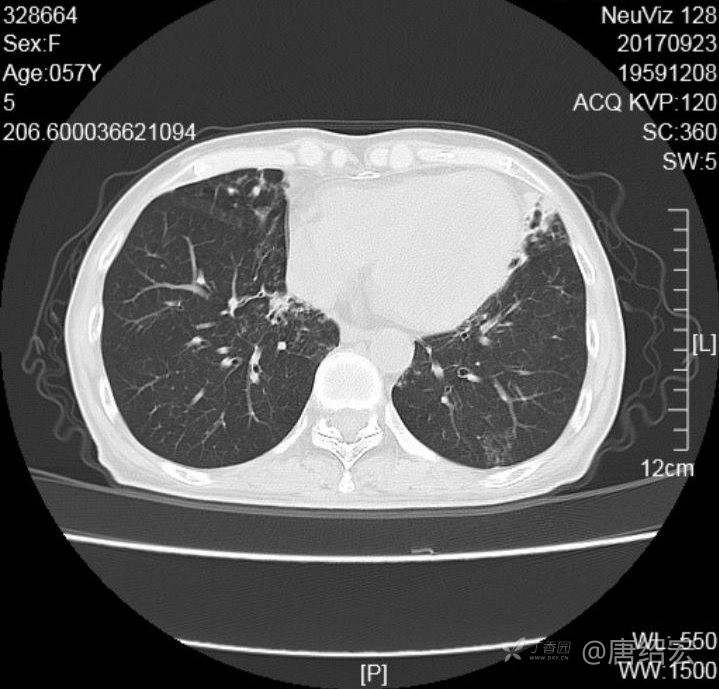

女,57岁,

主诉:发热、咳嗽、咯黄痰,胸闷3天入院。

铜绿假单胞菌性肺炎 (12)

铜绿假单胞菌感染 (20)